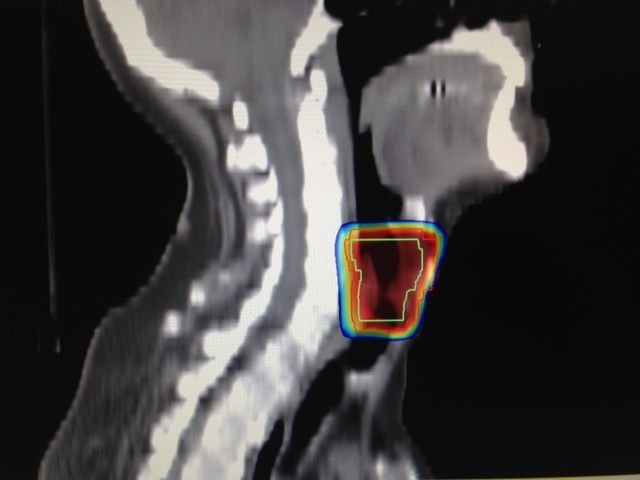

• Terapia de arco volumetrico modulado (VMAT)